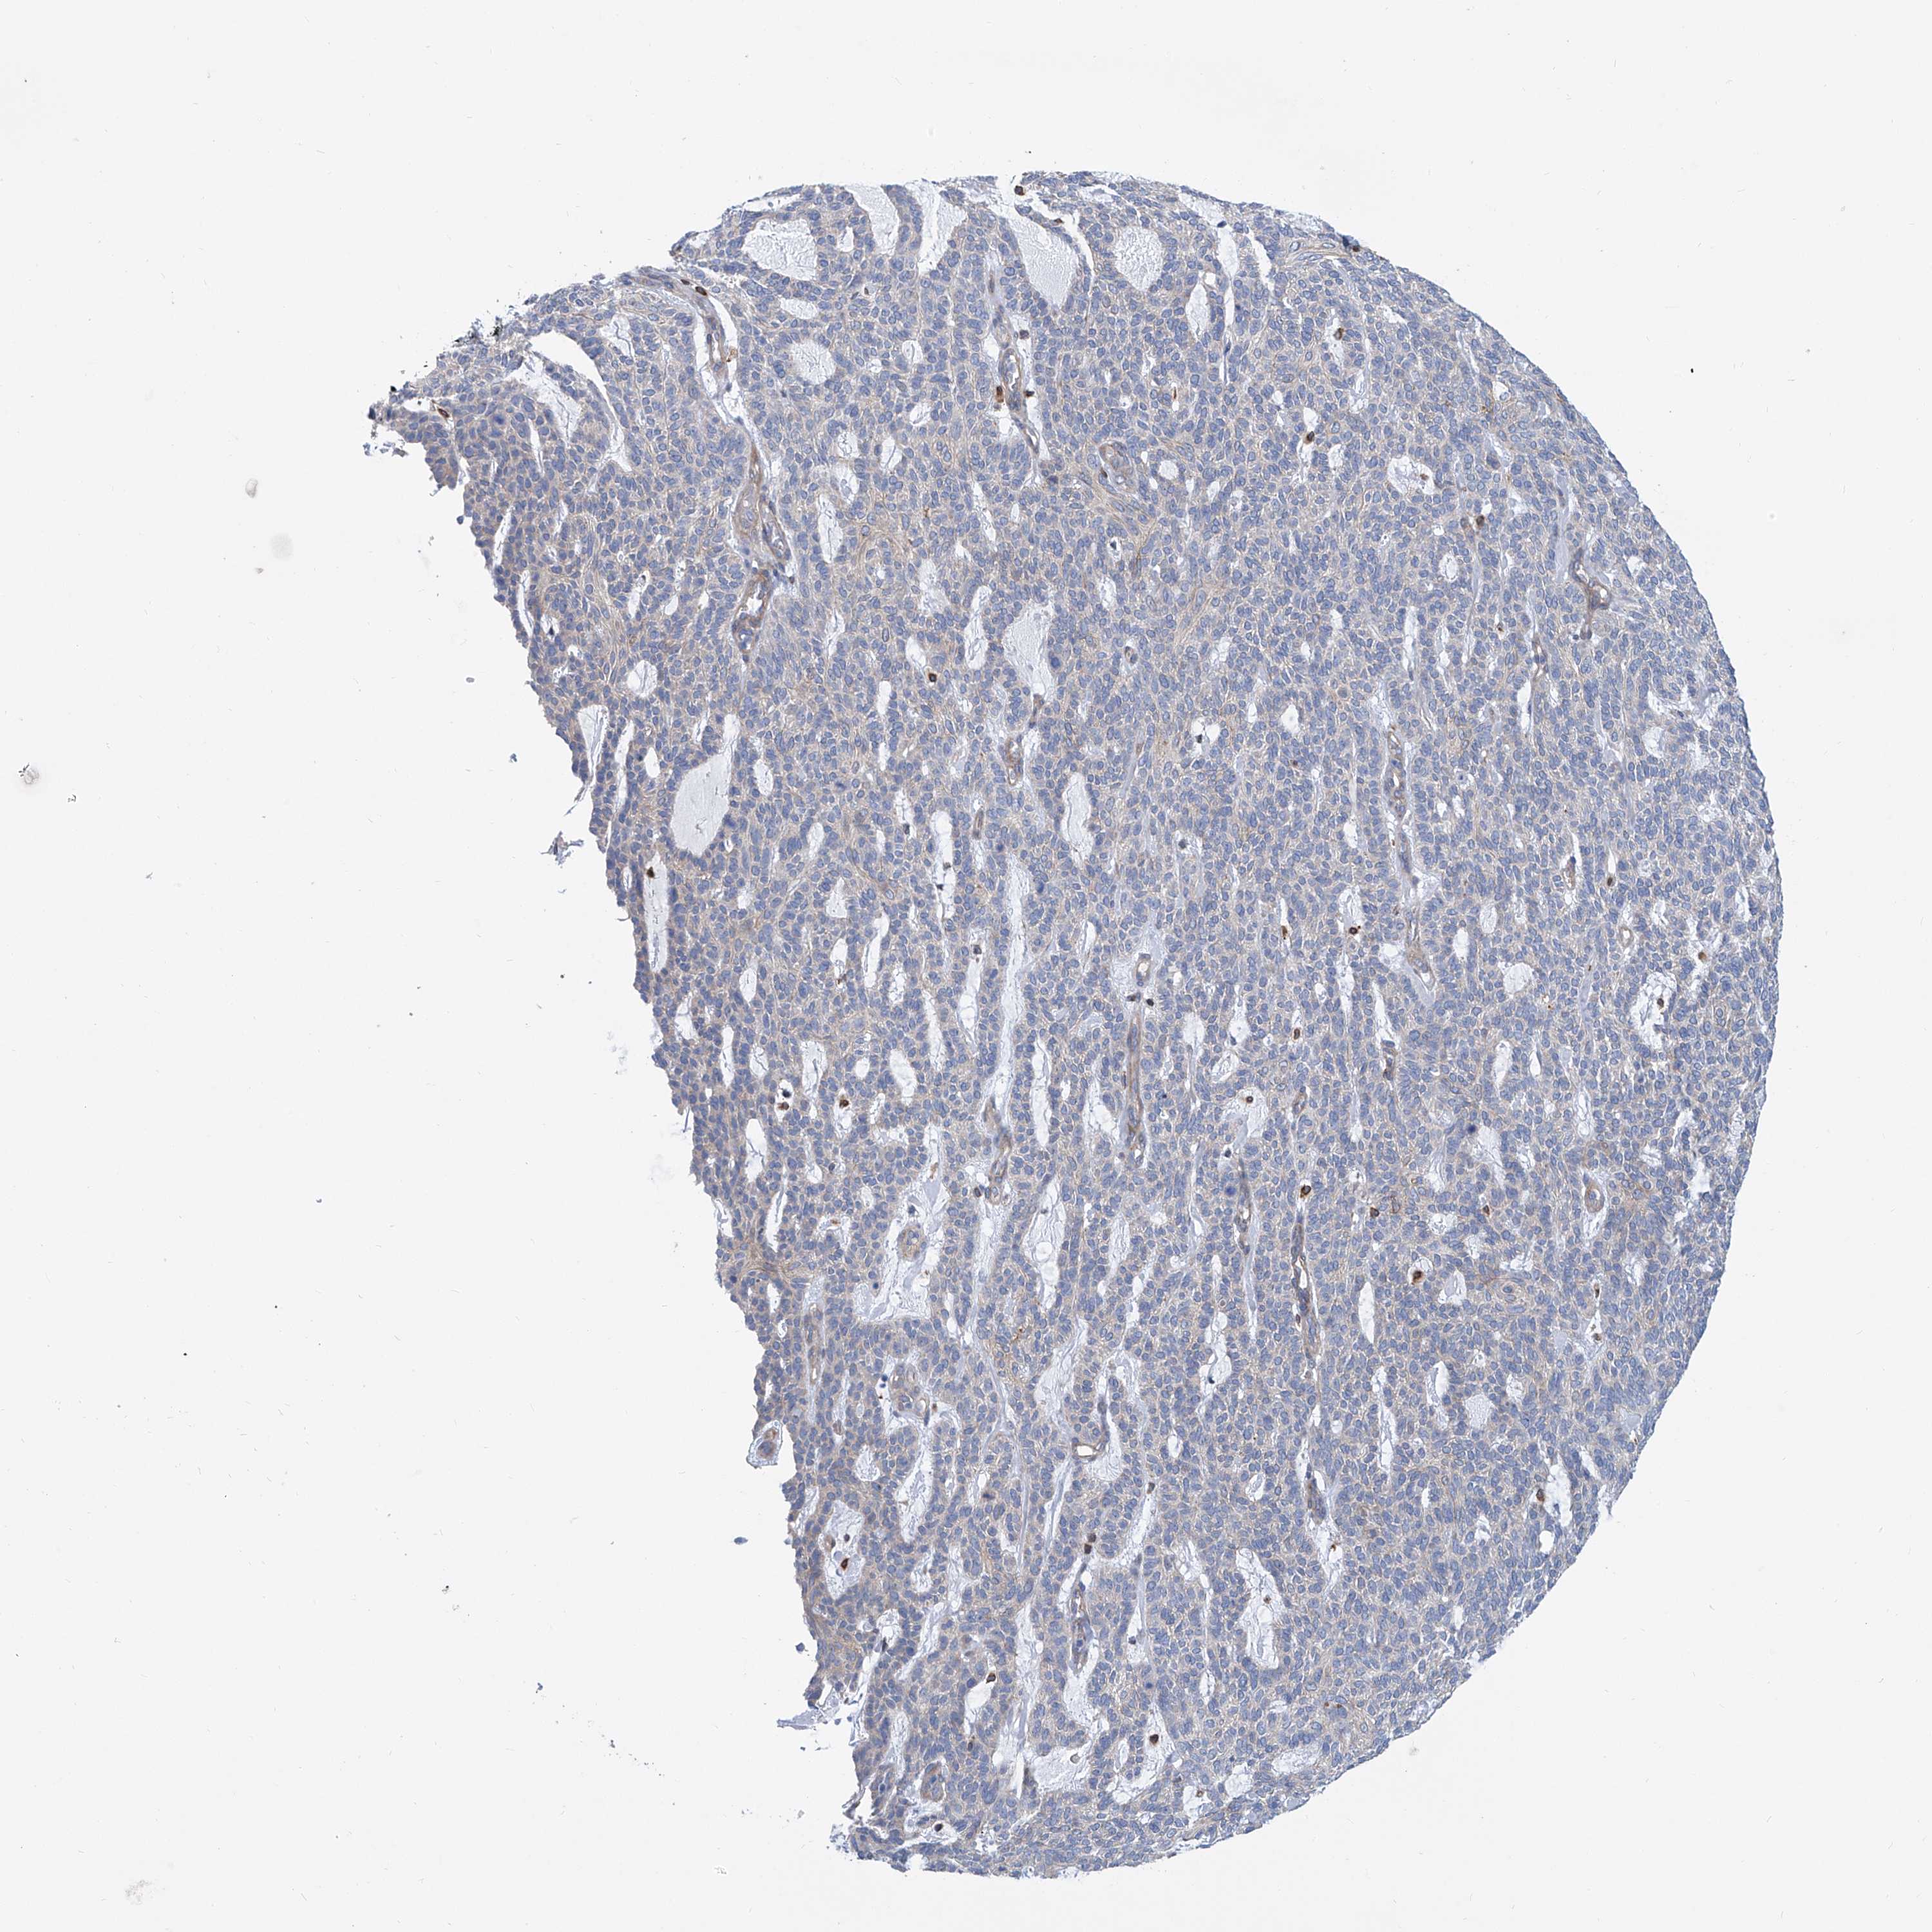

SKIN CANCER - Protein expressioni

A mouse-over function shows sample information and annotation data. Click on an image to view it in a full screen mode. Samples can be filtered based on level of antibody staining by selecting one or several of the following categories: high, medium, low and not detected. The assay and annotation is described here.

Antibody stainingi

Antibody staining in the annotated cell types in the current human tissue is reported as not detected, low, medium, or high, based on conventional immunohistochemistry profiling in selected tissues. This score is based on the combination of the staining intensity and fraction of stained cells.

Each image is clickable and will lead to virtual microscopy that enables deeper exploration of all samples and also displays staining intensity scores, fraction scores and subcellular localization as well as patient and tissue information for each sample.

Antibody HPA026726

Antibody HPA026764

Antibody CAB010907

Basal cell carcinoma

Squamous cell carcinoma, NOS

Squamous cell carcinoma, metastatic, NOS